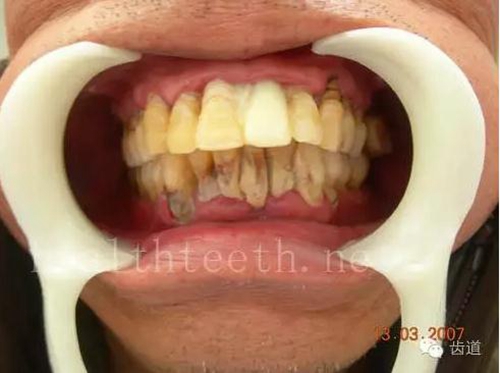

四環(huán)素牙

38.jpg

牙神經(jīng)治療后的牙齒變色